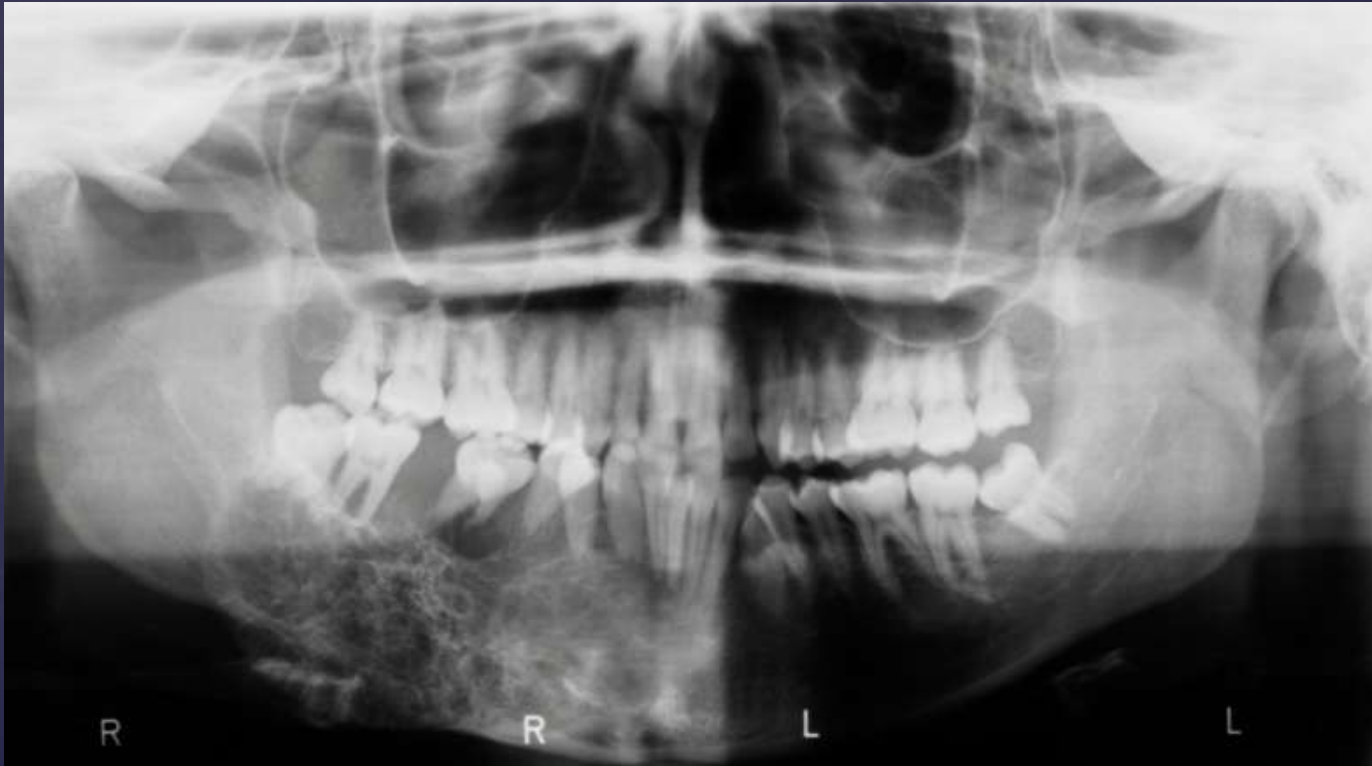

Compound –Complex Odontoma

Well defined

Mixed density, corticated

Combination of amorphous radiopaque mass and tooth like structures

Osseous expansion

Thinning of cortices

Displacement of teeth, unerupted tooth